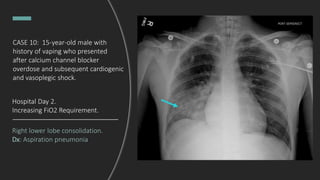

CASE 10: 15-year-old male with

history of vaping who presented

after calcium channel blocker

overdose and subsequent

cardiogenic and vasoplegic shock,

intubated and admitted to

pediatric ICU.

What do you see?

Hospital Day 2. Increasing

FiO2 requirement.

Right lower lobe consolidation.

Dx: Aspiration pneumonia

Hospital Day 2.

Increasing FiO2 Requirement.